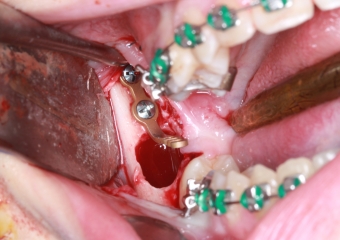

Extração dos 4 terceiros molares   - Instalação de placas de ancoragem - Clínica Cliniface

Extração dos 4 terceiros molares - Instalação de placas de ancoragem